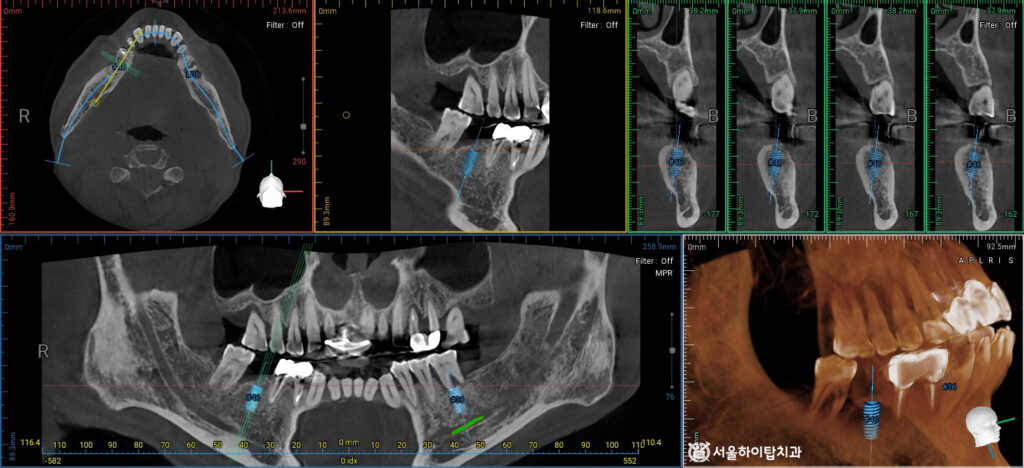

따라서 정밀 CT 촬영으로

임플란트가 식립될 위치를 확인하고,

잔존 치조골의 높이, 밀도, 두께까지

면밀하게 분석합니다.

현재 금속 기둥(픽스처)이

가상으로 심겨진 모습을 보면,

하치조신경과의 거리도 확보되어 있고,

안전한 식립이 가능함을 확인할 수 있습니다.

또한, 왼편 상악에서는

하악의 장기간 상실로 인해

정출이 있을 수 있는 위치였지만,

양옆 치아가 남아 있어

교합을 일부 유지할 수 있었기 때문에

정출도가 심하지 않은 상태였습니다.

따라서, 양쪽 모두 식립에 특이사항이 없어

간석오거리 치과 에서는 당일 임플란트를

동시에 식립할 수 있을 것으로 판단됩니다.